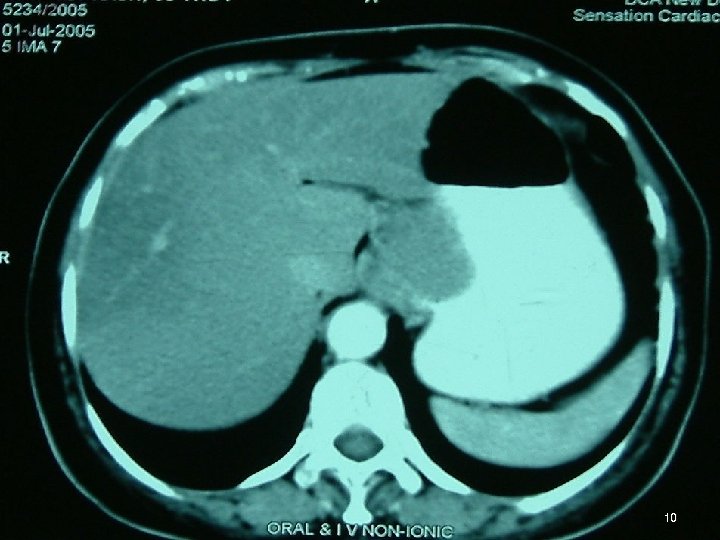

Investigations • • • Chest X Ray USG CECT EUS Ba Swallow 3

Diagnosis • FDG PET = mandatory ►FDG-PET CT scan is ideal • MD-CE-CT = image modality of choice for abdomen (if FDG-PET-CT is not available) • MR • Evaluate by Chol or RECIST criterion 46

Diagnosis • Polyp / Metastases of Lobular Breast CA in Ut • GIST, Lymphoma / 2 nd primary at GI jn